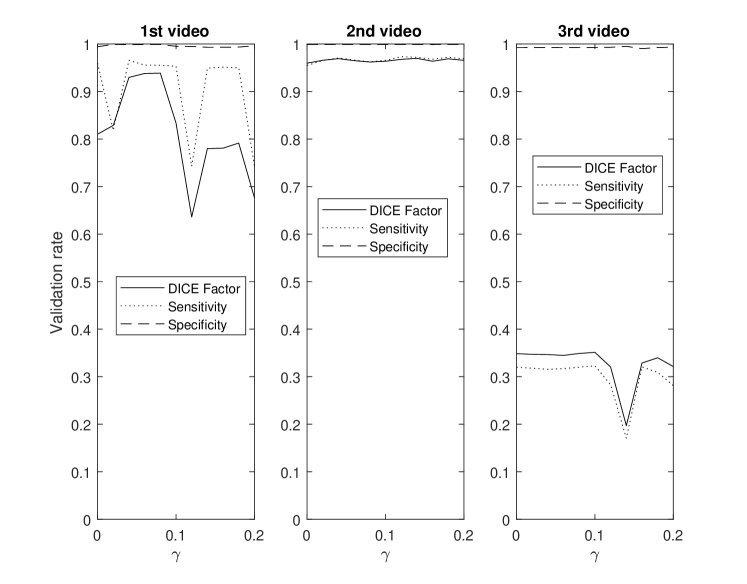

This section demonstrates the robustness of the algorithm for each parameter along with the relative importance of each parameter on the overall performance. This enables the identification and potential removal of weak features from the energy function in order to improve computational efficiency. For this study, the average DICE factor, sensitivity, and specificity of three different clips versus the initial parameters , , , , and are shown in Figs. 5-10. In the all of these figures, one can easily see that the specificity is always very close to one indicating a relatively small rate of .

In Fig. 7, all three videos provide their best performance at a between 0.04 and 0.08, hence, is set at 0.06. In two of the three test videos, the edge energy does not significantly improve the segmentation performance as the curves appear flat around likely resulting from indistinct edges and consequently, providing limited information to improve segmentation results.